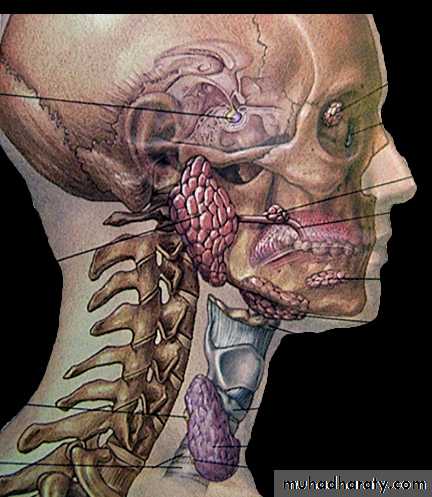

Dr Maitham H. KenberParotid

glandSubmandibular

glandSublingual

glandSalivary Glands Overview

• Major salivary glands

• a. Parotid gland• b. Submandibular gland

• c. Sublingual gland

Parotid gland

Located in the preauricular region and along the posterior surface of the mandible .Parotid gland is divided by the facial nerve into :

* superficial lobe overlying the lateral surface of the masseter

* deep lobe between the mastoid process of the temporal bone and the ramus of the mandible

Submandibular gland

Lies in digastric (submandibular) triangleDevided by mylohyoid muscle into

1.superficial lobe

2.deep lobe

Duct of submandibular (Wharton’s duct) from deep lobe pass between hyoglossus and mylohyoid m. to open at sublingual caruncle in the floor of the mouth lateral frenulum of the tongue

Sublingual gland

Sublingual Salivary glands

Smallest of the major salivary glands.Almond shape

Deep to the floor

of mouth mucosa.

It is drained by approximately

10 small ducts (Ducts of Rivinus)